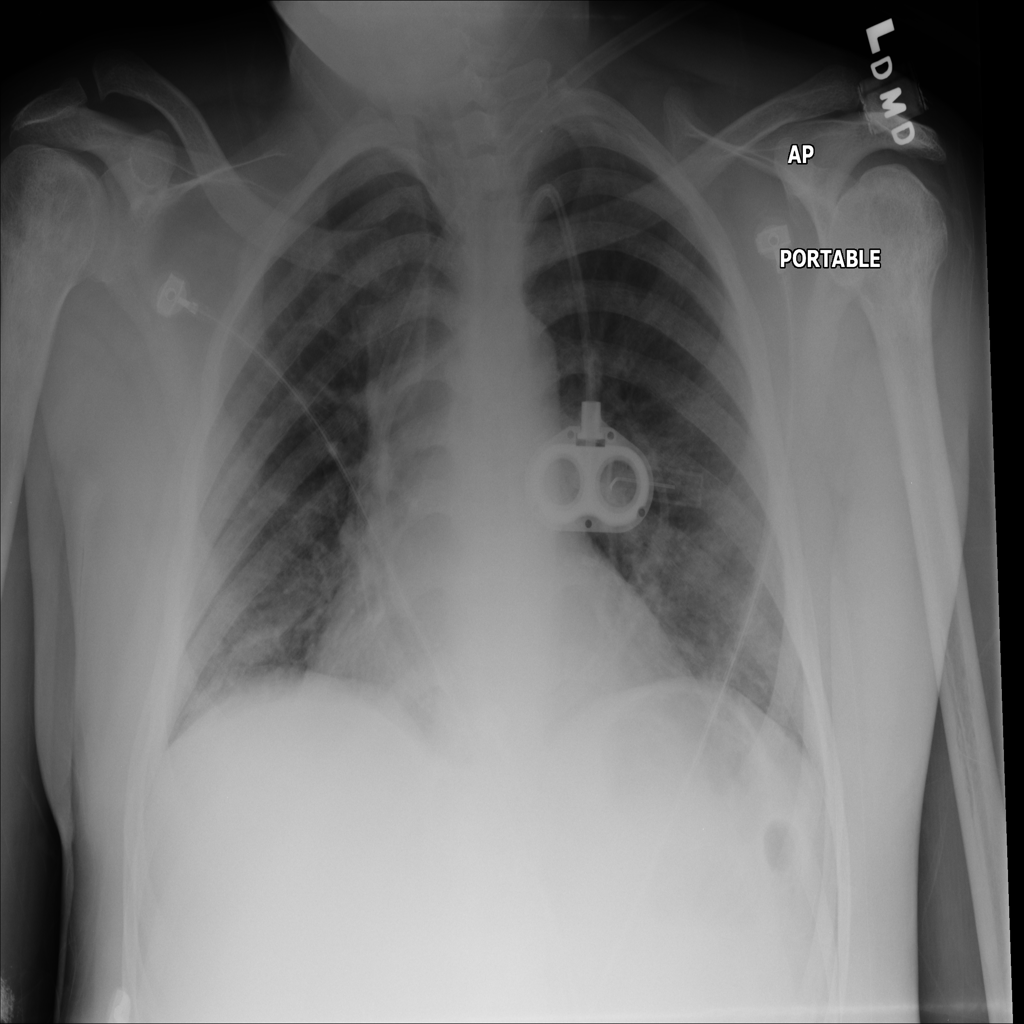

PAT-EBE1 · IMG-019Pneumonia

PAT-EBE1 · IMG-019

AP